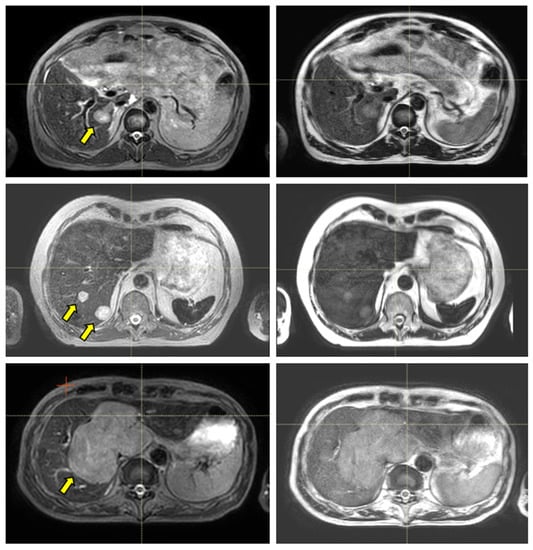

The ability to visualize moving targets with 2D cine imaging is depicted in Figure 5 for one pancreas case and three liver cases, as acquired with the btFFE, T1w-cine, and T2w-cine sequences. The quality of the cine data was critical as this imaging was used to derive and verify ITV margins and monitor setup during the online treatment sessions.

As depicted in Figure 5, the btFFE sequence often did not provide sufficient contrast to identify the target. Since this sequence is the only fast imaging option available for real-time monitoring in the Unity-TSM environment, any other cine sequence had to be acquired and evaluated on the MR console only. Thus, the target motion assessed with the T1w- and T2w-cine sequences was performed as an on-demand auxiliary process to the TSM. Another distinguishing factor was that the frame rates for T1w- and T2w-cine were 2 Hz and 3–4 Hz, respectively, compared to 5–6 Hz for btFFE. However, lengthening the cine acquisition up to 1 min allowed for the full sampling of the organ/target residual motion cycle under AC.

Figure 5. Sample data for four UGI patients highlighting the range of contrast available with the 3D cine sequences used for the quantification and monitoring of patient setup and target motion. Each row is for a different patient and shows either a coronal or sagittal view: (AD) corresponds to Patients 10, 15, 6, and 12, as per Table 1. The columns correspond from left to right to the MR planning data set identifying the target location, btFFE cine, T2w-cine, and T1w-cine.